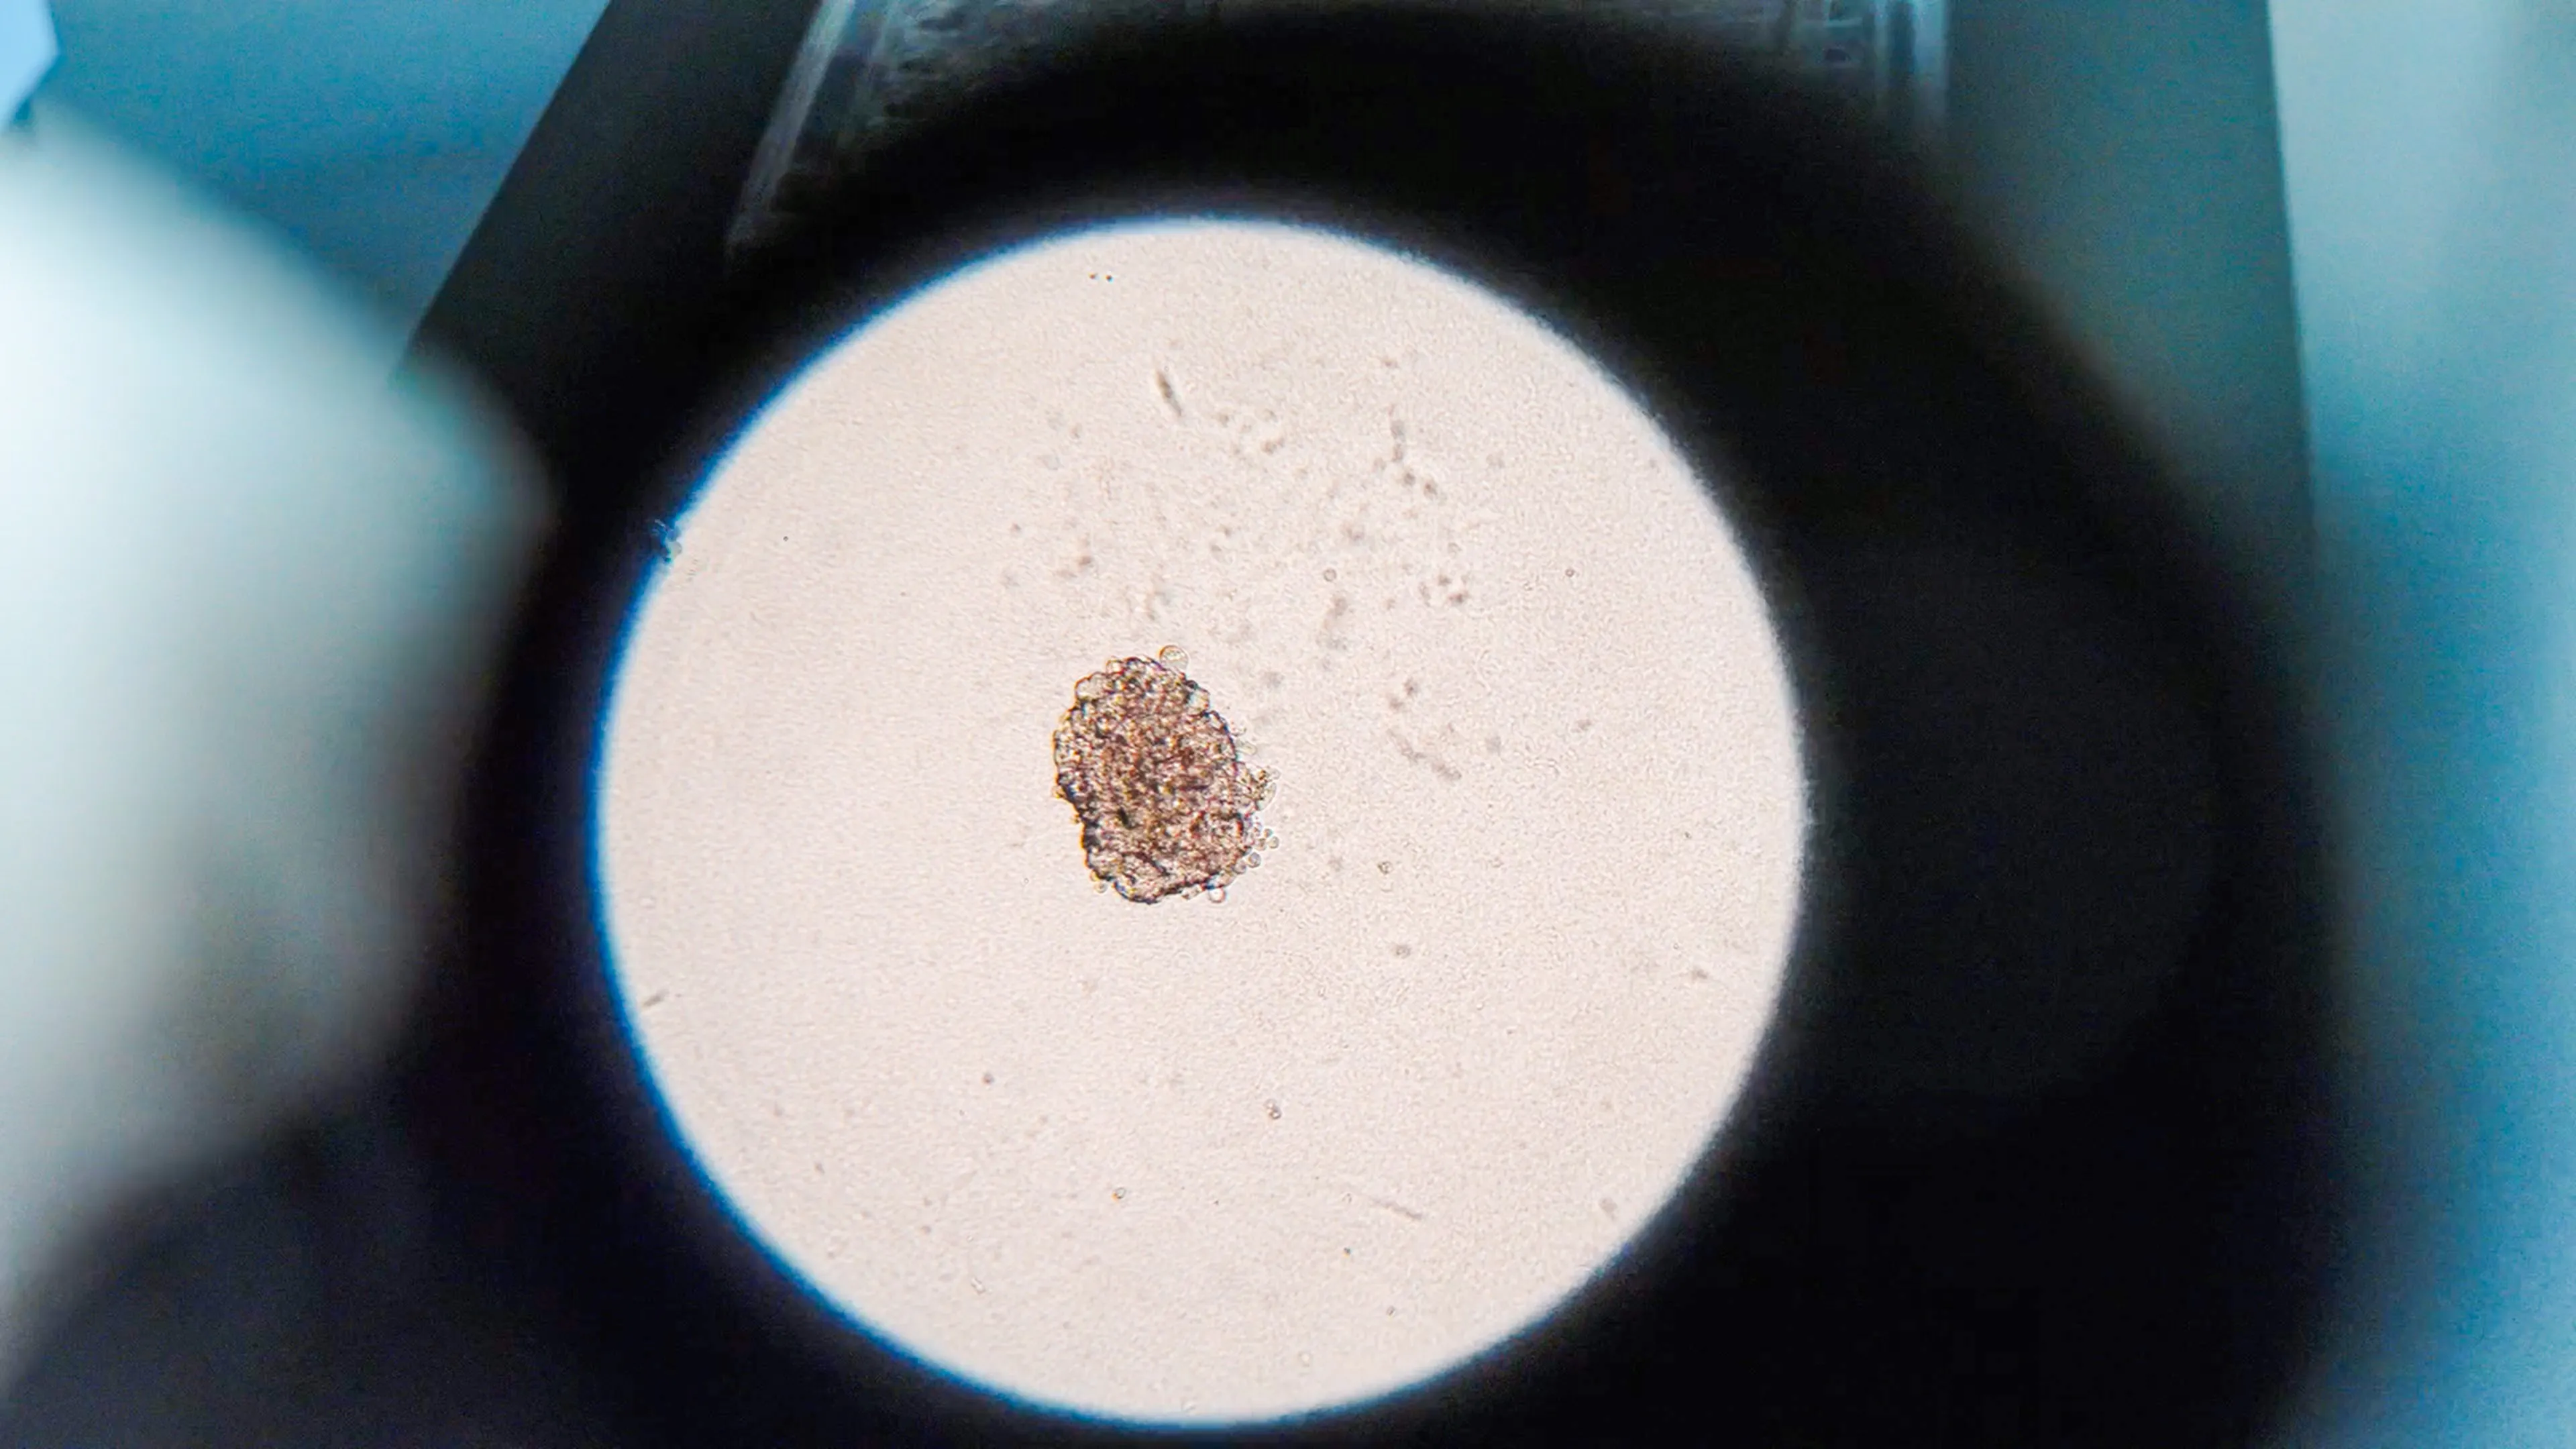

杜塞尔多夫大学 x VIKpro

Düsseldorf, Germany

2025 Nov